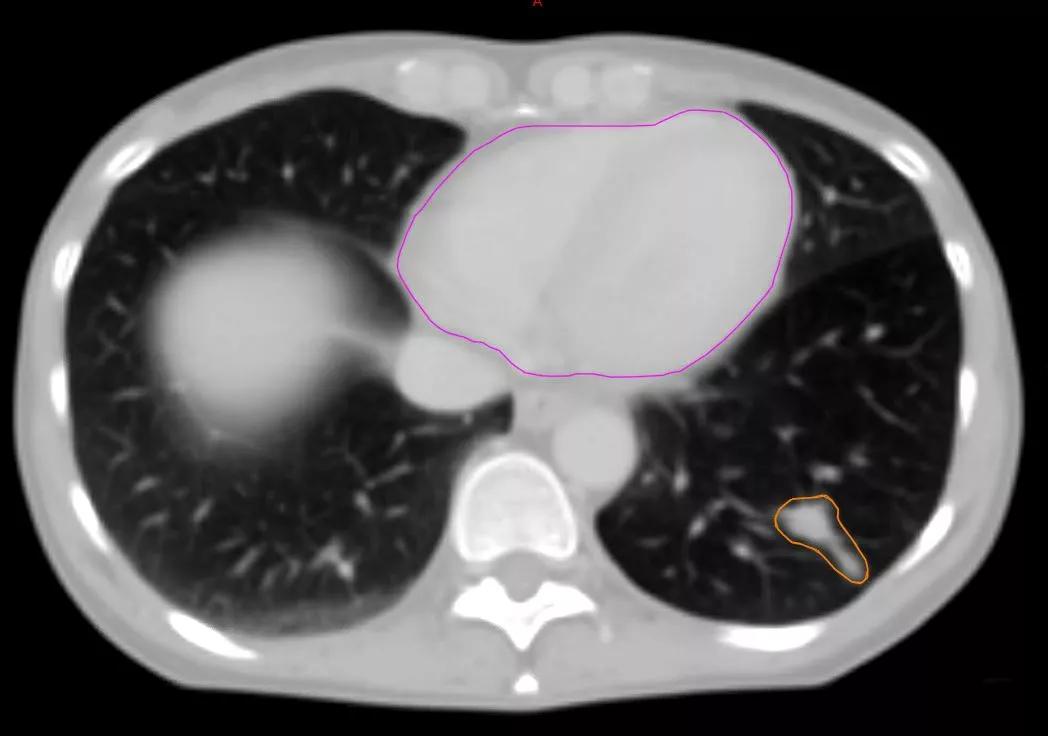

Tværsnit af brystkassen på en patient med lungekræft. Hjertet er markeret med lilla, og kræftsvulsten er markeret med orange. Scanningsfoto: Ditte Sloth Møller

Tværsnit af brystkassen. Hjertet er markeret med lilla, og kræftsvulsten er markeret med orange.

To scanningsfotos af den samme lungekræftpatient, der viser, hvor meget anatomien kan ændre sig:

Tværsnit af brystkassen hos samme patient, efter at den højre lunge er klappet sammen. Billedet viser, hvordan hele anatomien har ændret sig, og svulsten er skubbet til en ny placering inde i den sammenklappede lunge.